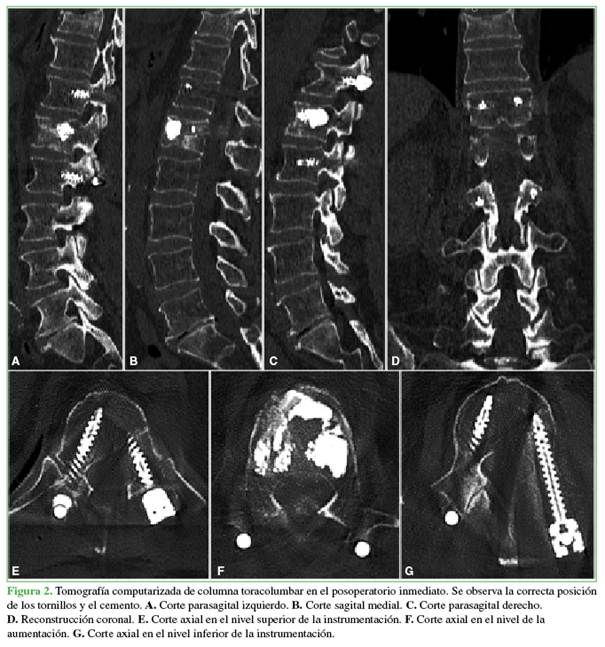

Imágenes posoperatorias

En una tomografía computarizada, se confirma la correcta posición de los tornillos y la ausencia de fuga de cemento intracanal (Figura 2). No se observan signos de compresión del canal vertebral.